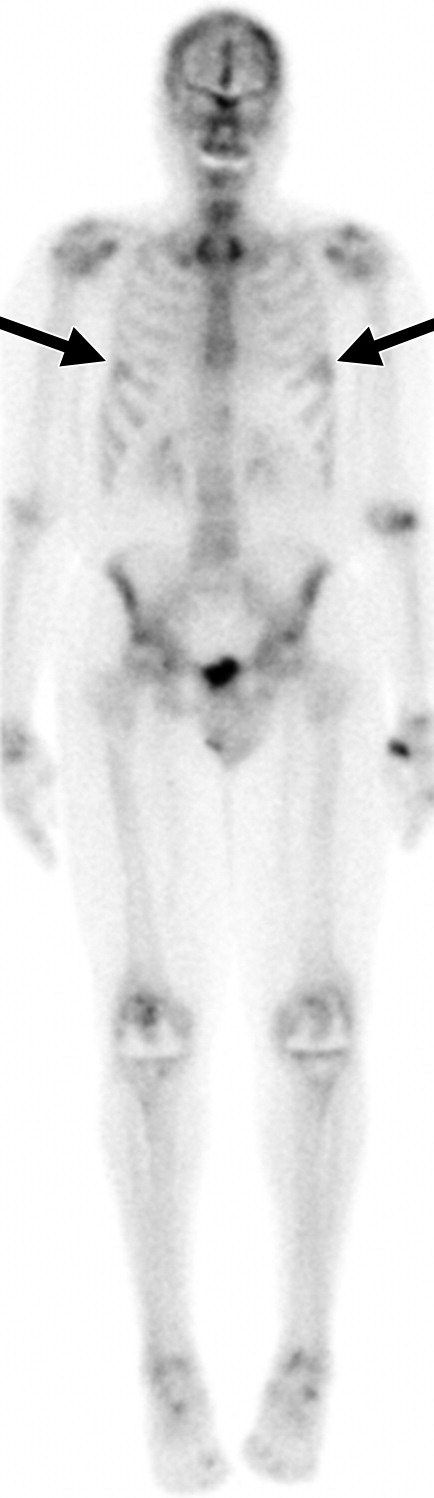

Scintigrafia scheletrica whole-body normale.

Scintigrafia ossea di un paziente con metastasi ossee da tumore prostatico.